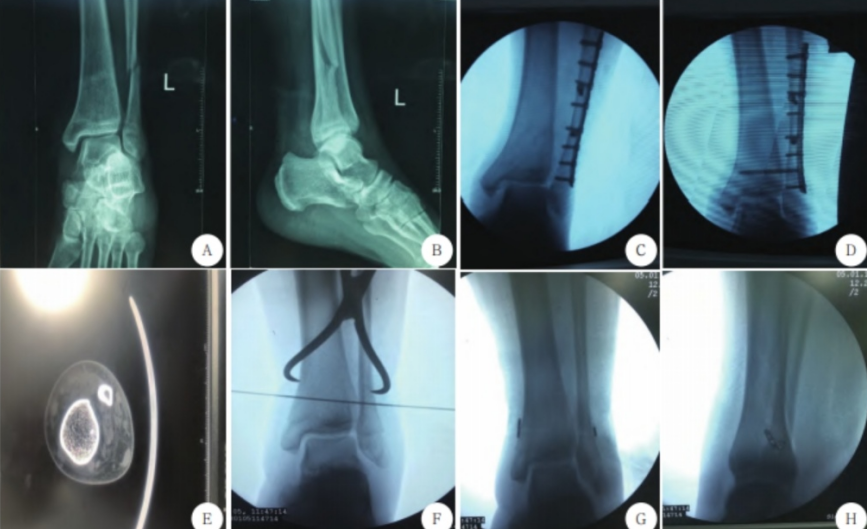

上图为下胫腓联合损伤不同固定方式,图A-D患者行下胫腓螺钉内固定术;图E-H患者行下胫腓Endobutton带袢钢板内固定术。(来自参考文献2)